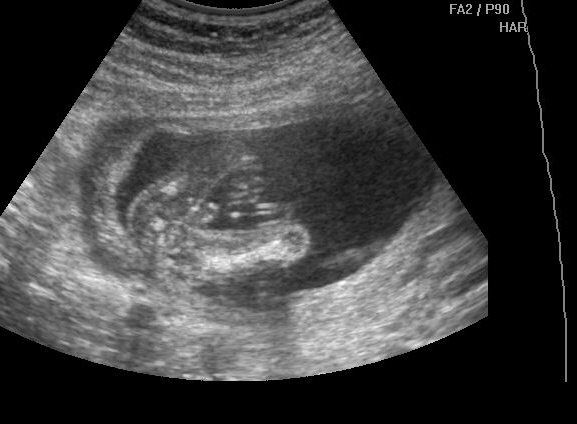

Csak gyorsan beköszönni jöttem.... Köszönjük a drukkokat, FIAM lesz, ez már 100000%. Boti szépen terpesztett, mutatta a fütyit, és a zacsirész is látszott, a golyók még nem látszanak, de a zacsi már megvolt, a fütyi meg szépen ágaskodott.... Imádom.

Méretekre pontosan 16+6 nak felel meg, így 1 nap a különbség csak, ez tökéletes a nő szerint. Kb. 20cm lehet már a kis manóseggű, és 17,5dkg. :D

Egy kép a szerelmemről:D

A Fütyink alulról nézve :D

Kép

Botikám, szerelmem :D